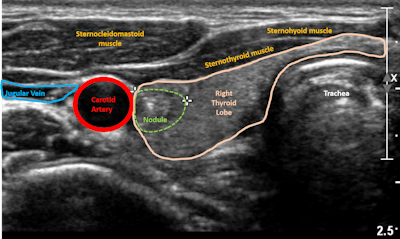

The prevalence of thyroid nodules in the general population is as high as 67%, the authors noted. Most nodules are benign, but once one is detected, it must be evaluated via ultrasound. Nodules larger than 1 cm are often recommended for fine-needle biopsy; some are evaluated with molecular genetic testing, which, although less invasive, is expensive.

The researchers investigated whether a machine-learning algorithm developed on a Google platform could be used with thyroid ultrasound to serve as a quick and inexpensive first screen for thyroid cancer. They trained the algorithm on 556 thyroid nodule images from 121 patients who underwent ultrasound-guided fine-needle biopsy and, subsequently, molecular testing.

Based on a particular gene panel, the molecular testing categorized 43 of the nodules as high risk and 91 as low risk. The group then tested the algorithm on a different set of 53 images to determine how well it could classify thyroid nodules compared with molecular test results.